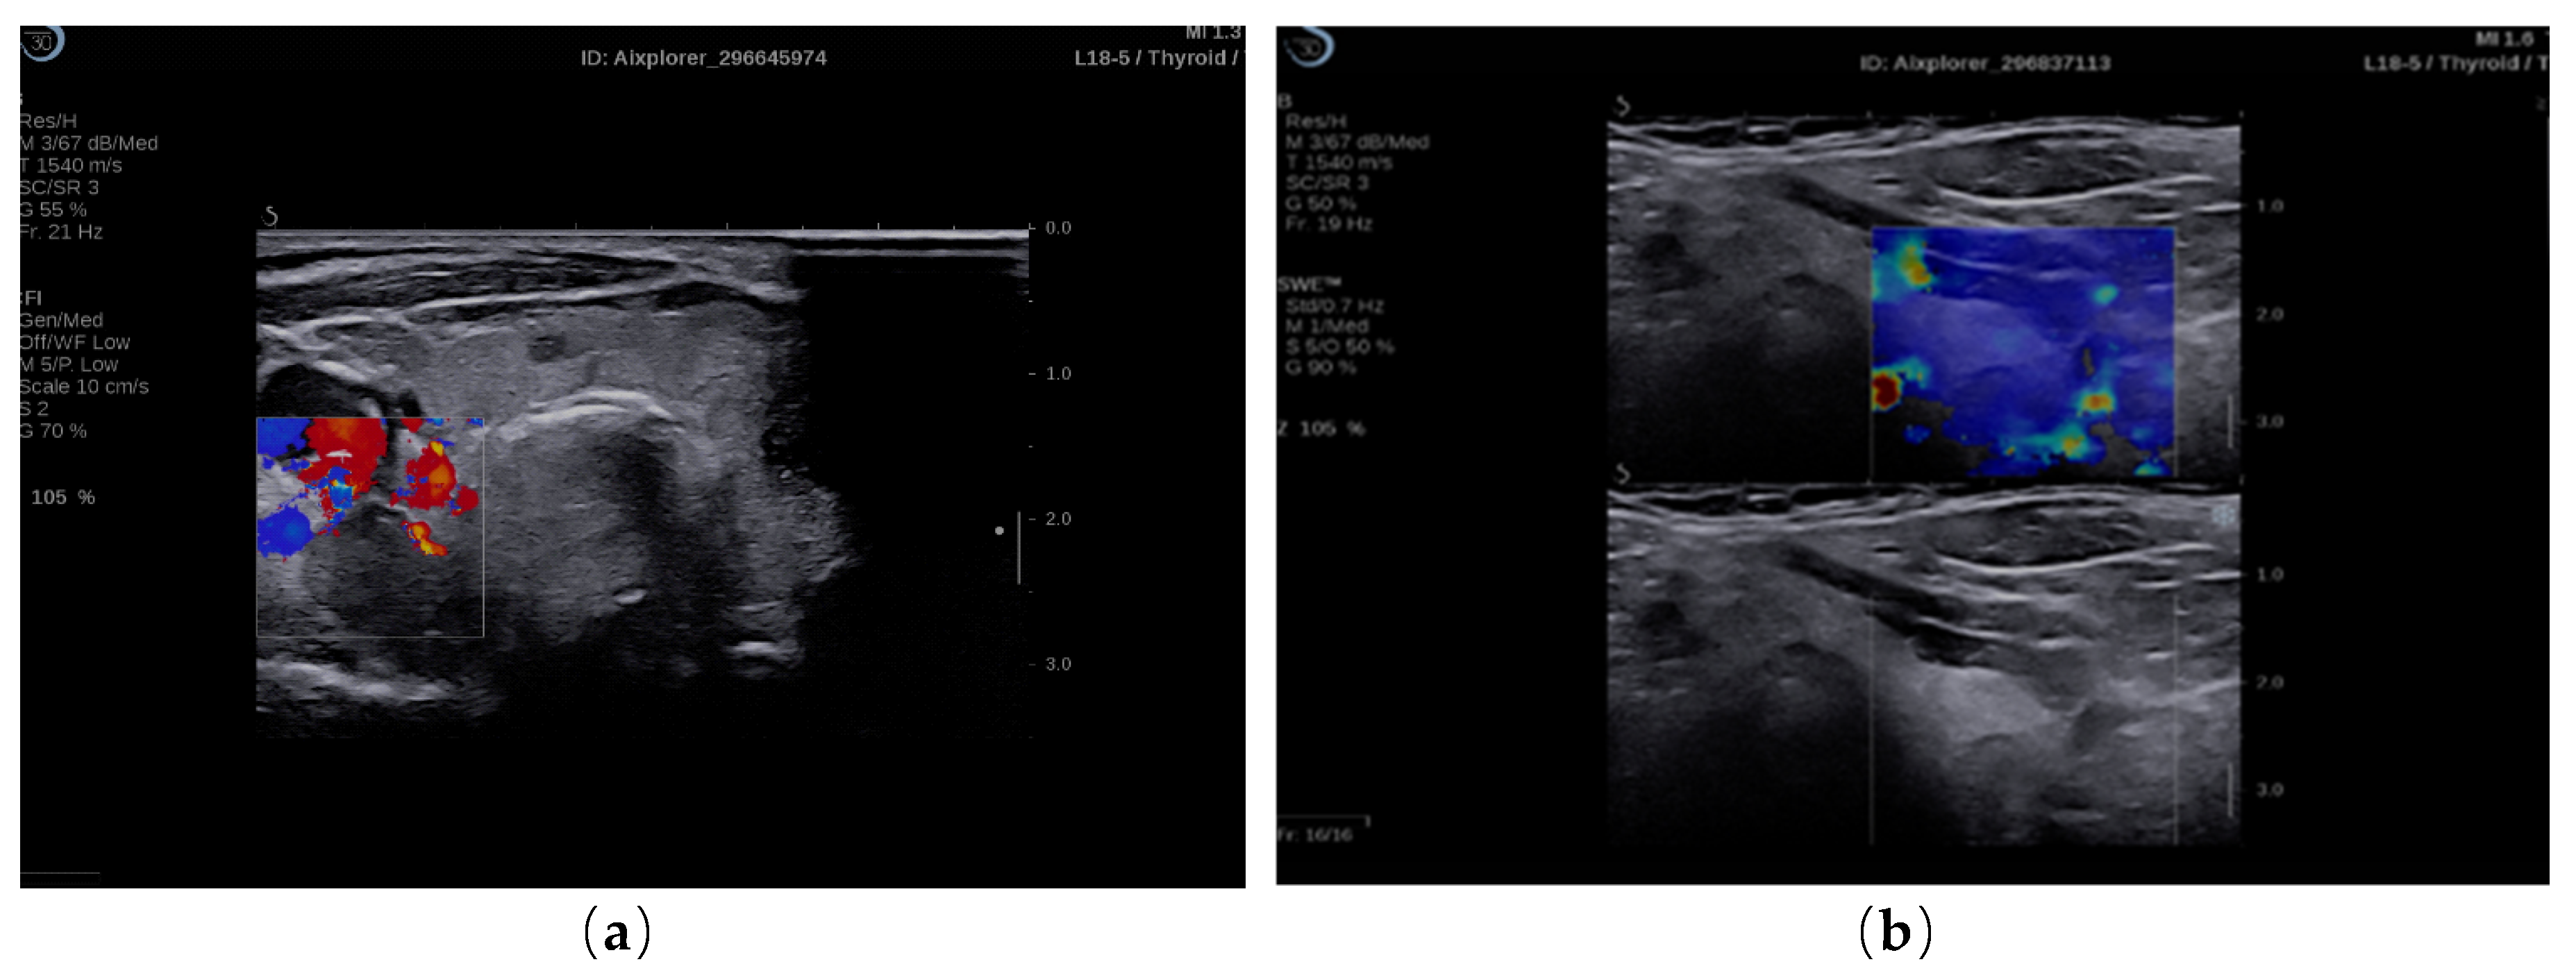

2.4. Elastography Exam

3.1. SWE Results